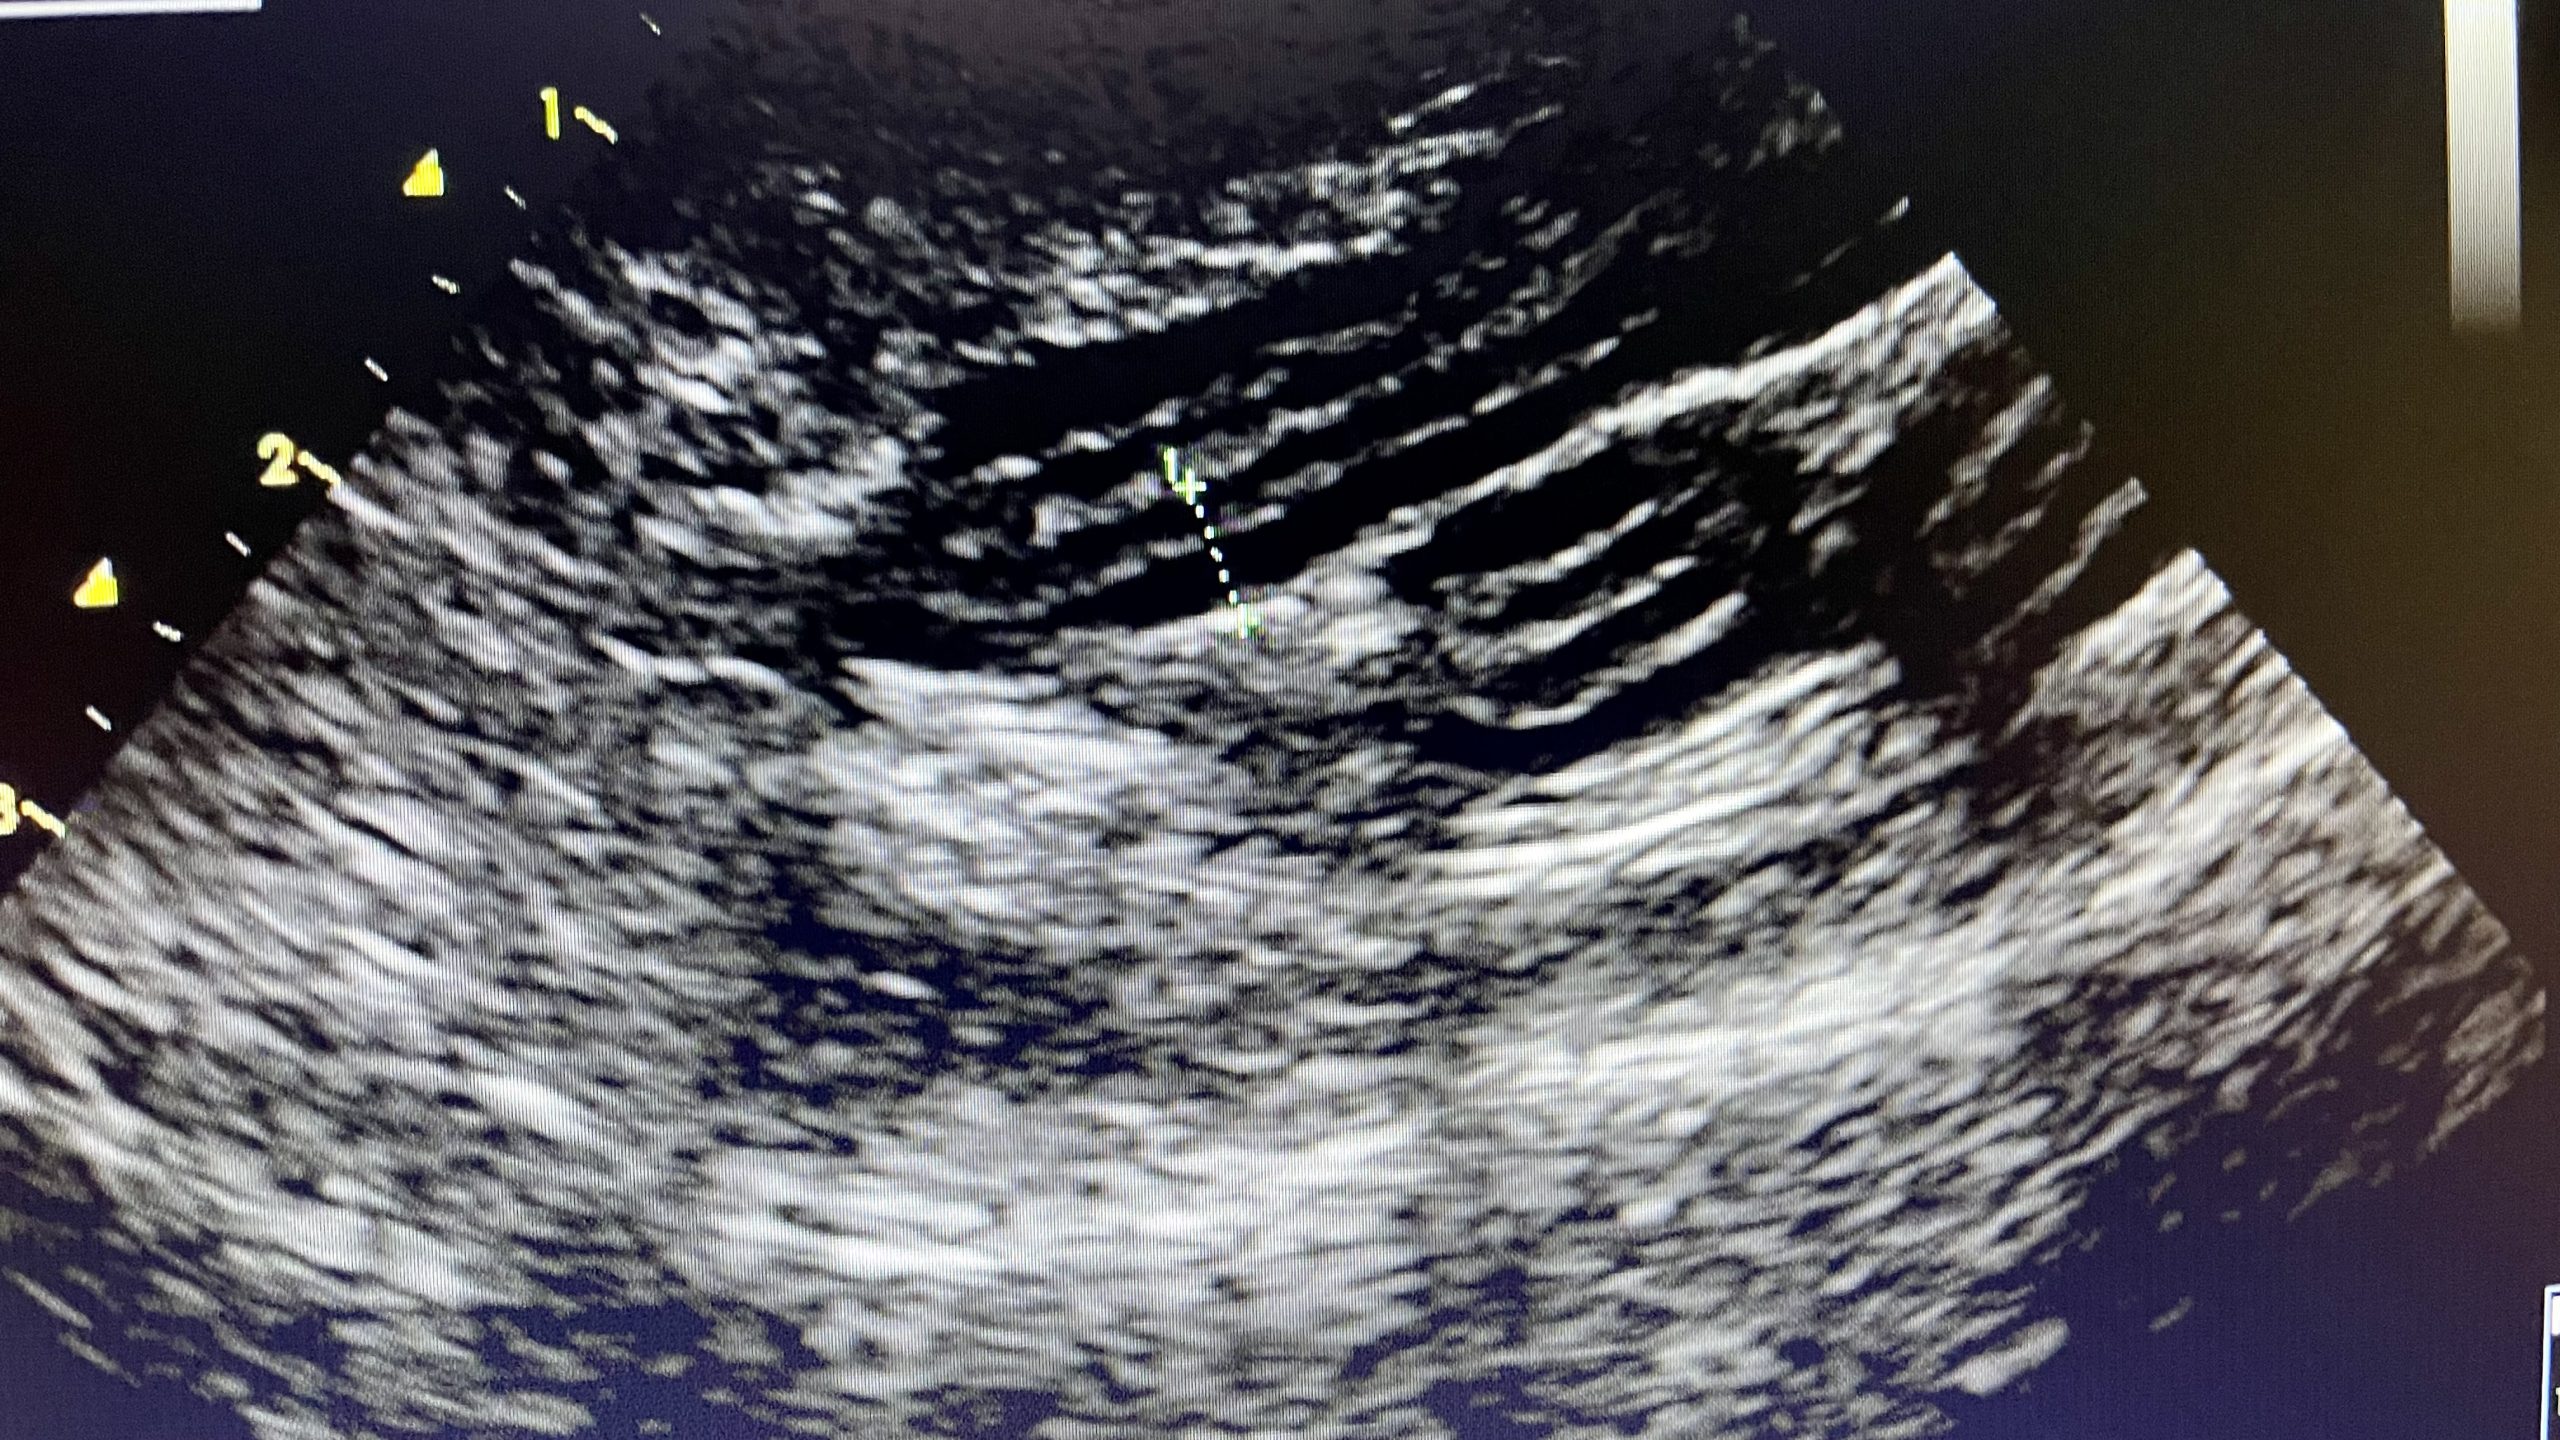

Imaging

We have digital radiography on site which means we can take an x-ray of your pet and have an exquisitely detailed image, on screen, in a few seconds. This means your pet is sedated or anaesthetised for a shorter period of time which helps reduce any risks. We have conventional x-ray as above, and also dental x-ray. The standard of care in veterinary dentistry has improved over the last decade, and good quality dental work does require support from dental x-rays, especially so for cats where they can have hidden dental lesions below the gumline.

Also in our imaging suite, is an outstanding ultrasound machine, the standard of which would meet that required for referral cardiology. The better the machine, the more accurate the images and report will be, which ultimately means more robust diagnoses and better outcomes for our animal patients. Investing in quality medical equipment and experienced, passionate staff to be the best for your beloved pets is the Whisker & Woof way.